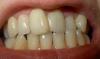

salofa Опубликовано 8 ноября, 2007 Автор Поделиться Опубликовано 8 ноября, 2007 (изменено) Не знаю правильно ли сфоткали, ну вот что-то типа того.Это перекрестный прикус? Изменено 8 ноября, 2007 пользователем salofa Ссылка на комментарий

Премоляр Опубликовано 8 ноября, 2007 Поделиться Опубликовано 8 ноября, 2007 если я скажу вам что имеет место соотношение моляров справа по 2 классу,слева по 3 классу,обратная резцовая окклюзия 21,22,тесное положение зубов на вер. и ниж. челюстях..Это что то изменит?Или вместо брекетов у вас есть какая то другая альтернатива??? Ваша фраза "...патология прикуса по фото.." напоминает мне объявление в газете-"сниму порчу и сглаз по фото.Результат гарантирую" Ссылка на комментарий

salofa Опубликовано 8 ноября, 2007 Автор Поделиться Опубликовано 8 ноября, 2007 если я скажу вам что имеет место соотношение моляров справа по 2 классу,слева по 3 классу,обратная резцовая окклюзия 21,22,тесное положение зубов на вер. и ниж. челюстях..Это что то изменит?Или вместо брекетов у вас есть какая то другая альтернатива??? Ваша фраза "...патология прикуса по фото.." напоминает мне объявление в газете-"сниму порчу и сглаз по фото.Результат гарантирую" Вот теперь спасибо доктор! Только все-таки не назвали какой прикус у меня: обратный, перекрестный, открытый и т.д. Вот пожалуйста с точки зрения этой классификации. Ссылка на комментарий

Премоляр Опубликовано 9 ноября, 2007 Поделиться Опубликовано 9 ноября, 2007 Прямой 1 Ссылка на комментарий